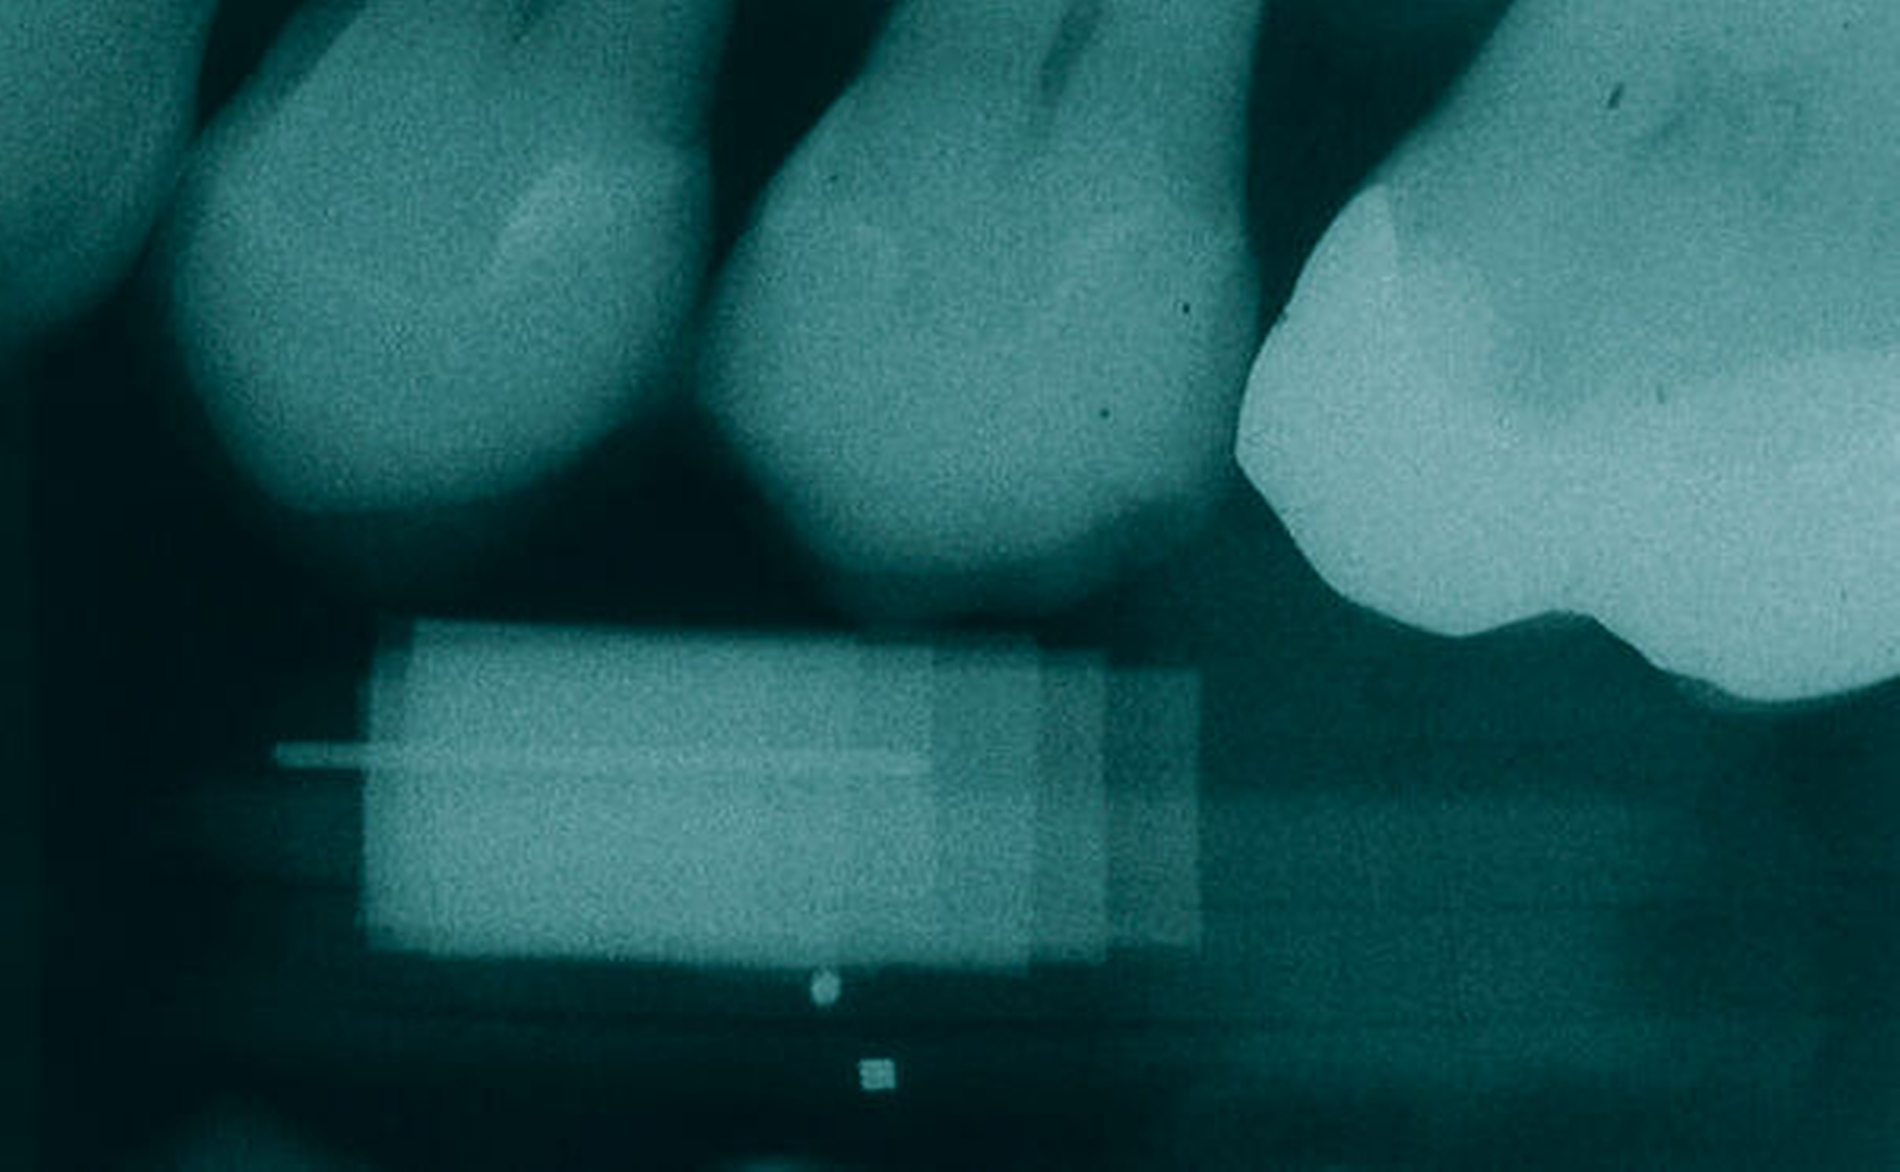

Werden verschiedene Zugangslappentechniken wie Instrumentierung unter Sicht mit Lappenbildung (Open Flap Debridement, OFD), Lappen mit paramarginaler Inzision (modified Widman Flap, MWF, Abbildungen 1 und 2), und Papillenerhaltungslappen (Abbildung 3) als konservative parodontalchirurgische Interventionen ohne signifikanten Weich- und Hartgewebsverlust hinsichtlich der Reduktion der TST verglichen, so bestehen kaum Unterschiede. MWF und OFD wurden in drei randomisierten klinischen Studien verglichen und nur eine davon hatte eine höhere Taschensondierungstiefenreduktion durch den MWF zum Ergebnis [Sanz-Sanchez et al., 2020].

Diese Fragestellung in der Leitlinie widmet sich dem Vergleich der Ergebnisse nach Lappenoperation mittels Zugangslappen (Abbildung 3), also Lappenbildung ohne gezielten Gewebsverlust, und resektiver Parodontalchirurgie – mit gezieltem Gewebsverlust, jedoch ohne zusätzliche Materialien zur parodontalen Regeneration [Polak et al., 2020]. Dabei werden alle chirurgischen Verfahren mit Resttaschen ab 5 mm nach vorheriger subgingivaler Instrumentierung verglichen. Bei der Betrachtung werden MWF (Abbildung 1), Excisional New Attachment Procedure (ENAP) in der Gruppe der Zugangslappen geführt. Die Gruppe der resektiven Parodontalchirurgie besteht aus auch zum Teil älteren Verfahren mit deutlicher Veränderung der Gingiva- und der Knochenkontur.